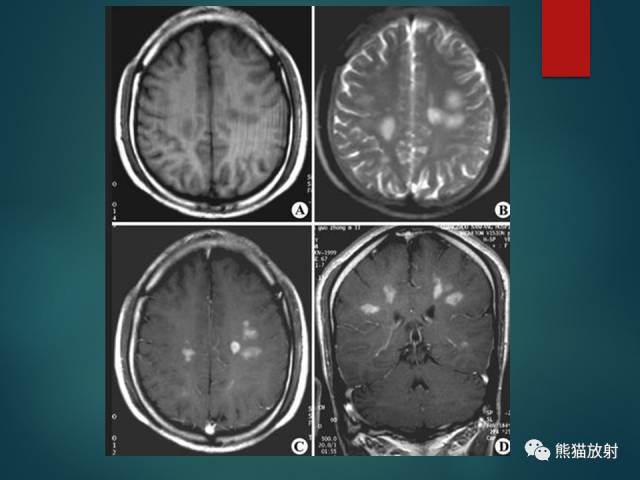

- 多发性硬化(MS):中青年女性;症状发作与缓解交替出现;直角脱髓鞘征;不同时期脱髓鞘斑块表现不一,急性期有强化。

- 脑白质疏松(LA):小动脉病变导致的白质纤维脱髓鞘;T2-FLAIR呈较高信号,DWI无弥散受限;常两侧对称,脑室周围明显。

- 腔隙性脑梗死(LACI):颅内小动脉及穿支动脉狭窄或痉挛;T2-FLAIR呈高信号;DWI急性期弥散受限;基底节、脑干及丘脑多见。